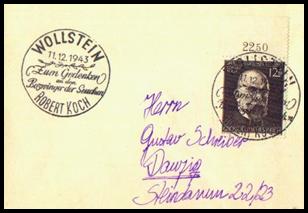

Robert koch 1843 – 1910

German scientist and Nobel laureate,

who founded modern medical bacteriology, isolated several disease-causing bacteria,

including those of tuberculosis, and discovered the animal vectors of a number

of major diseases.